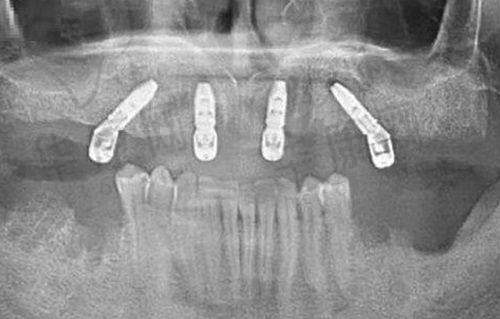

在术后的复诊过程中,刘鹏医生每次都会认真检查我的种植体情况,还会用专精的设备查看植体和牙槽骨的结合情况。他说我的修复情况良好,让我继续保持。而且北海柏乐口腔还提供“终身维保”服务,术后会定期免费给我拍片检查植体状态,有问题随时处理。这让我觉得特别安心,不用担心种植牙后期会出现什么问题。